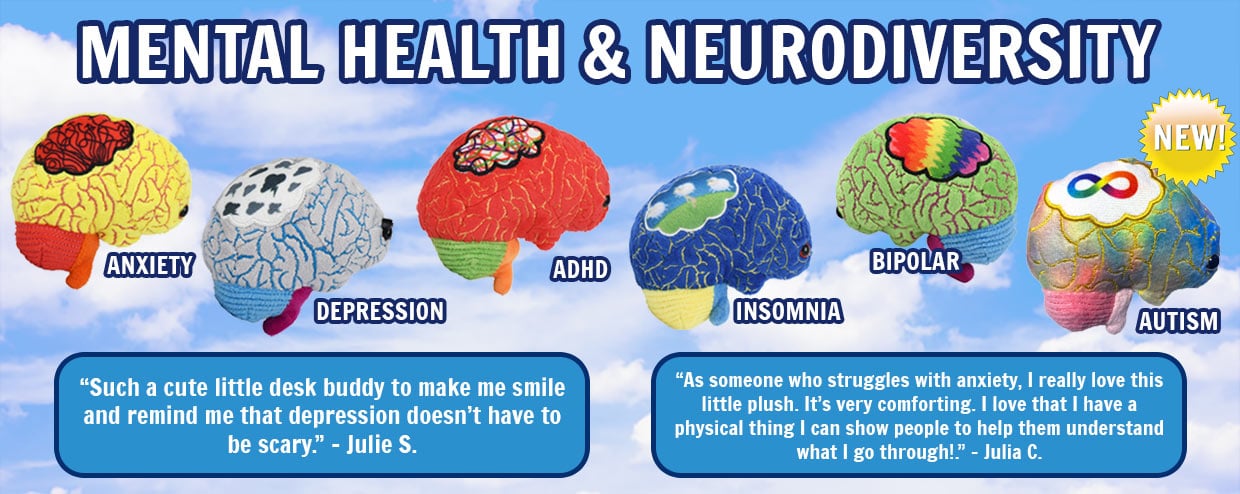

- 250 microbes, organs, cells, and health topics

- Educational tools for students and healthcare professionals

- Feel Good and Get Well wishes for family and friends